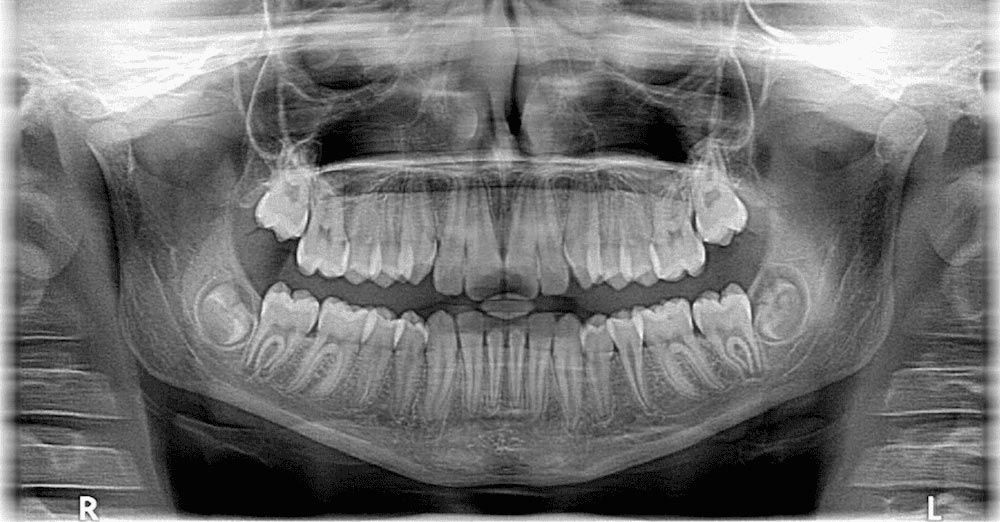

TMJ (Jaw Pain)

TMJ (Temporomandibular disorder) is a muscle disorder that contributes to pain and injury associated with chewing, and other jaw movements. TMJ is most common in people under the age of 45, and more common in women than men. It’s important to treat TMJ, with its potential to lead to other issues like headaches and dental conditions, and at Dynamic Physiotherapy we offer a range of options to reduce pain and muscle spasm, and to improve the function of affected areas.